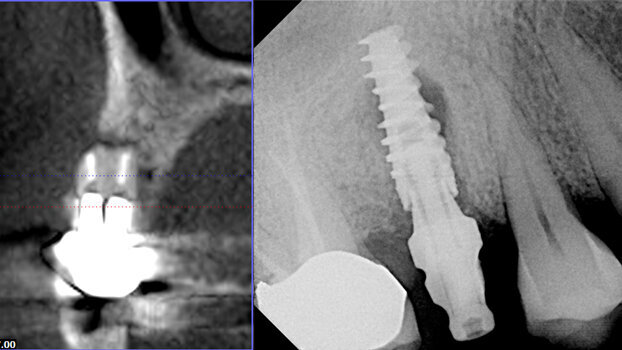

Severe buccal destruction easily detected on a 3-D cross-section from Cone Beam (GXCB-500), and successful implant placement verified by a digital X-ray (DEXIS).

3-D reveals narrow ridges and provides precise measurements for safer placement.